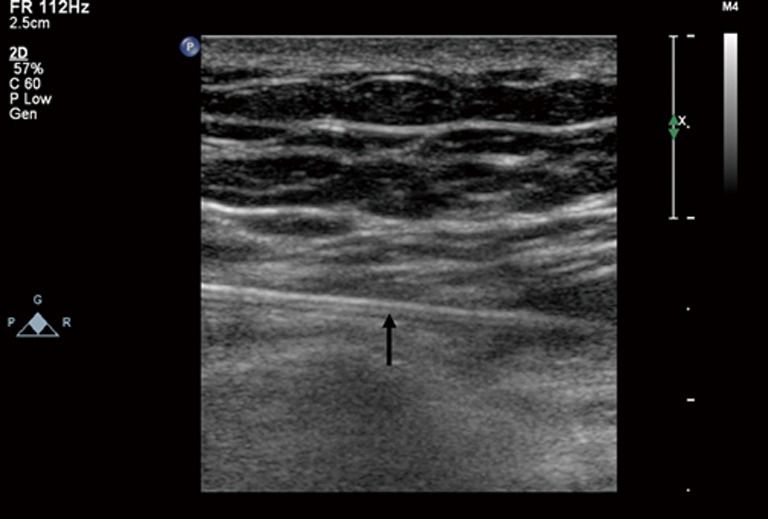

Figure 3.

Transthoracic echocardiography showed one needle (arrow) was inserted through the chest wall into the pericardial space.